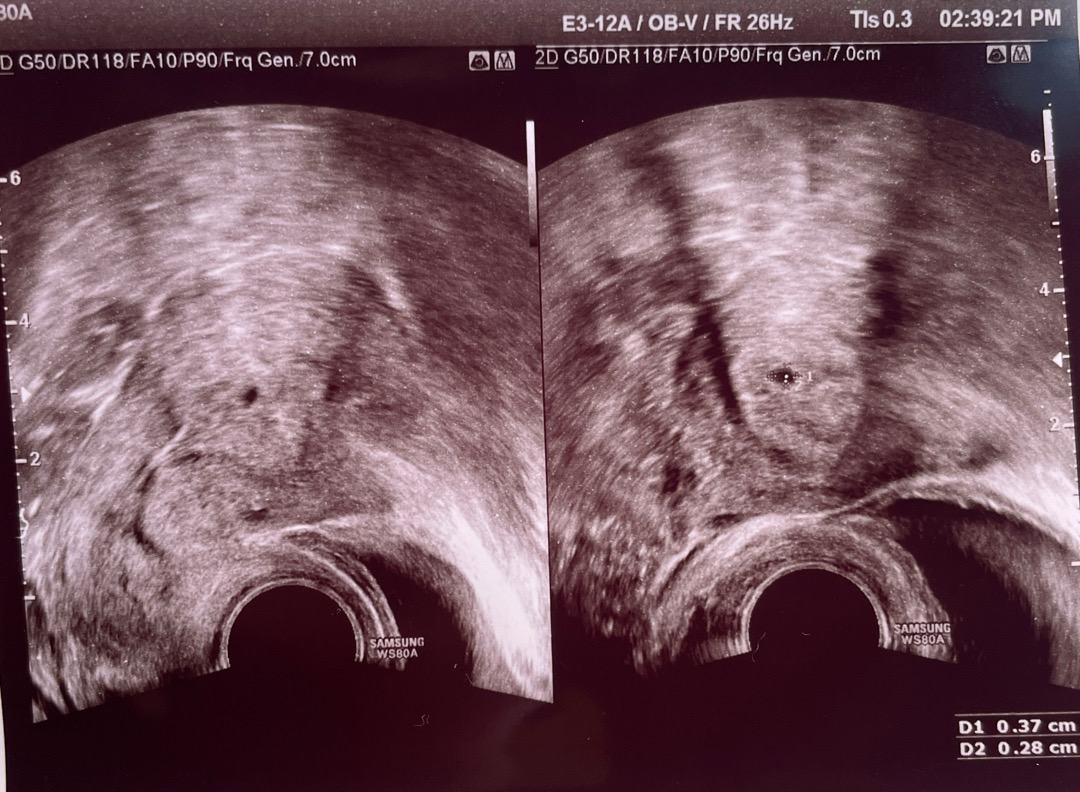

아기집 보고왔어요!

12.28. 마지막생리시작일이고, 1.24. 착상혈 보고 1.27.테스트기 해보니 2줄이라 오늘 병원가서 초음파 보고왔는뎅 제가 생리주기가 33일 정도로 길어서 애기집이 아직 작다구하네용!!ㅎㅎㅎ 그래도 우리 뽀또 보고오니깐 진짜 임신했구나 하는 마음에 엄청 기뻐용❣️